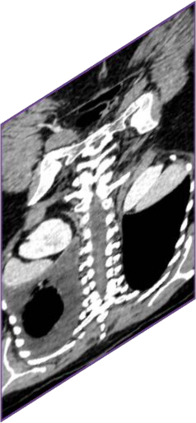

Due to the constraints of the imaging device and high cost in operation time, computer tomography (CT) scans are usually acquired with low intra-slice resolution. Improving the intra-slice resolution is beneficial to the disease diagnosis for both human experts and computer-aided systems. To this end, this paper builds a novel medical slice synthesis to increase the between-slice resolution. Considering that the ground-truth intermediate medical slices are always absent in clinical practice, we introduce the incremental cross-view mutual distillation strategy to accomplish this task in the self-supervised learning manner. Specifically, we model this problem from three different views: slice-wise interpolation from axial view and pixel-wise interpolation from coronal and sagittal views. Under this circumstance, the models learned from different views can distill valuable knowledge to guide the learning processes of each other. We can repeat this process to make the models synthesize intermediate slice data with increasing inter-slice resolution. To demonstrate the effectiveness of the proposed approach, we conduct comprehensive experiments on a large-scale CT dataset. Quantitative and qualitative comparison results show that our method outperforms state-of-the-art algorithms by clear margins.